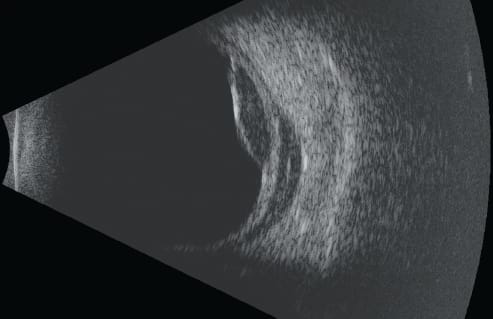

An ophthalmic ultrasound system evaluates ocular structures more clearly by providing images of all aspects of the anterior segment. It provides images of the eye and tissues around and behind the eye to determine the presence of pathology when doctors are prohibited from viewing it directly due to opacity of the cornea, lens, or the vitreous gel that fills the eye.

The Eye Cubed™ is used in conjunction with CT or MRI for imaging orbital tumors, optic nerve abnormalities, and to locate “foreign bodies” that get lodged in the eye or orbit from accidents. The ultrasound is currently the only method to obtain a critical view of the posterior segment when a dense cataract or vitreous hemorrhage is present in the eye.

The unique amplifier and probe design allow this system to achieve the industry’s highest signal-to-noise ratio. Because noise is reduced to a minimum, details of even the finest ocular structures become visible — including blood and inflammatory cells — during an examination of the eye.